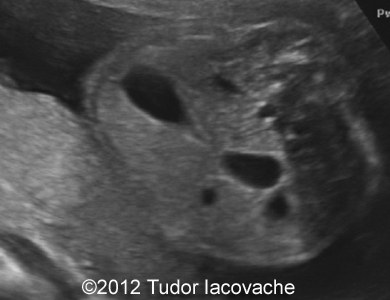

At 22 weeks the scan was suggestive of duodenal stenosis, with "double bubble" sign , no other anomalies, normal amniotic fluid. Karyotype was performed and was normal 46XX. The pregnancy continued with no problems and normal amniotic fluid.

The images and video clip are of the 22-week scan and shows the typical double bubble with dilation of the proximal duodenum and communication with the stomach.

Image 1-4: